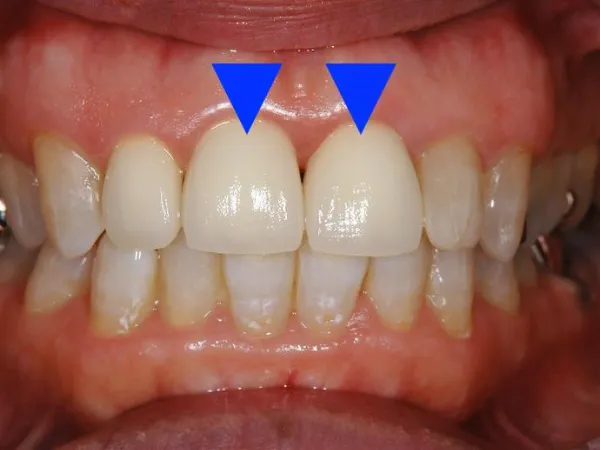

メタルボンド 中身を金属で作り、 外側にセラミックを張り付けたクラウンです。 | メリット ・強度が高い ・自然な仕上がり ・変色しない デメリット ・裏から見ると金属が見える ・金属アレルギーあり ・金属が溶けて歯茎が黒くなる ・セラミックに比べて虫歯、歯周病になりやすい |